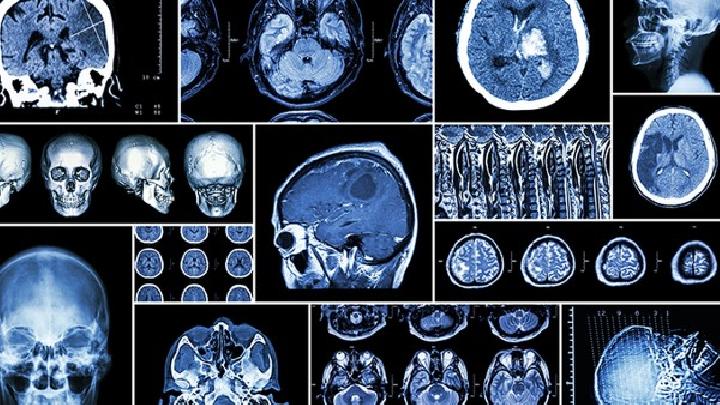

定期進行腦部影像學檢查:監(jiān)測病情變化,及時發(fā)現(xiàn)并處理任何進展。